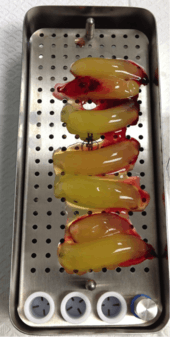

Blood-derived growth factors have been used in medicine and oral surgery for more than twenty years with an abundance of scientific data supporting its role in soft and hard tissue regenerations. APRF introduced by Dr. Choukroun represents the fourth improved generation of such technology and has been widely use in the field of dentistry and oral surgery. The advantages of APRF are of multiple folds: Unlimited amount (only 10 millilitres (0.35 imp fl oz; 0.34 US fl oz) per tube harvested), no risk of rejection or disease transmission (using your own blood), high noble type of healing (autogenous growth factors and hematopoietic stem cells).

Technique

A small amount of blood (10 millilitres (0.35 imp fl oz; 0.34 US fl oz) per tube) is harvested and spun in a centrifuge for eight minutes at 1300 rpm. A fibrin clot packed with blood-derived growth factors, extra cellular matrix and hematopoietic stem cells is fabricated and implanted into the gums above the area of gum recession. Advanced platelet-rich fibrin will promote the patient's own gums to fabricate more gum thus eliminating the need to harvest gums from the roof of the mouth or the use of allografting tissue.